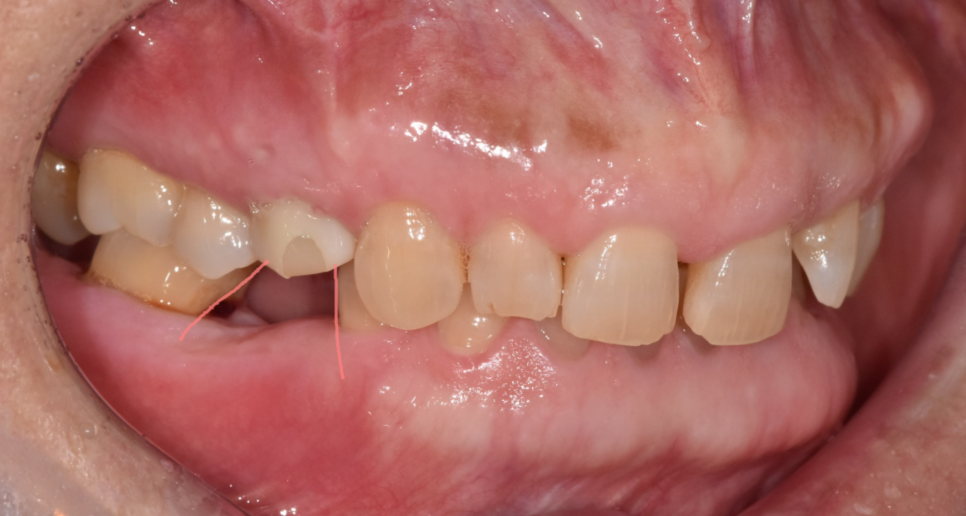

볼을 씹은 모습

누구나 식사를 하다가 한번쯤은

볼 씹힘을 경험하셨을겁니다.

치아가 상실되고 이가 없는 시간동안

볼 살이 치아 쪽으로 밀려 들어옵니다.

그런데 보철을 끼우게 되면

밀려들어온 살이 적응하지 못한채로

씹을 수 있습니다.